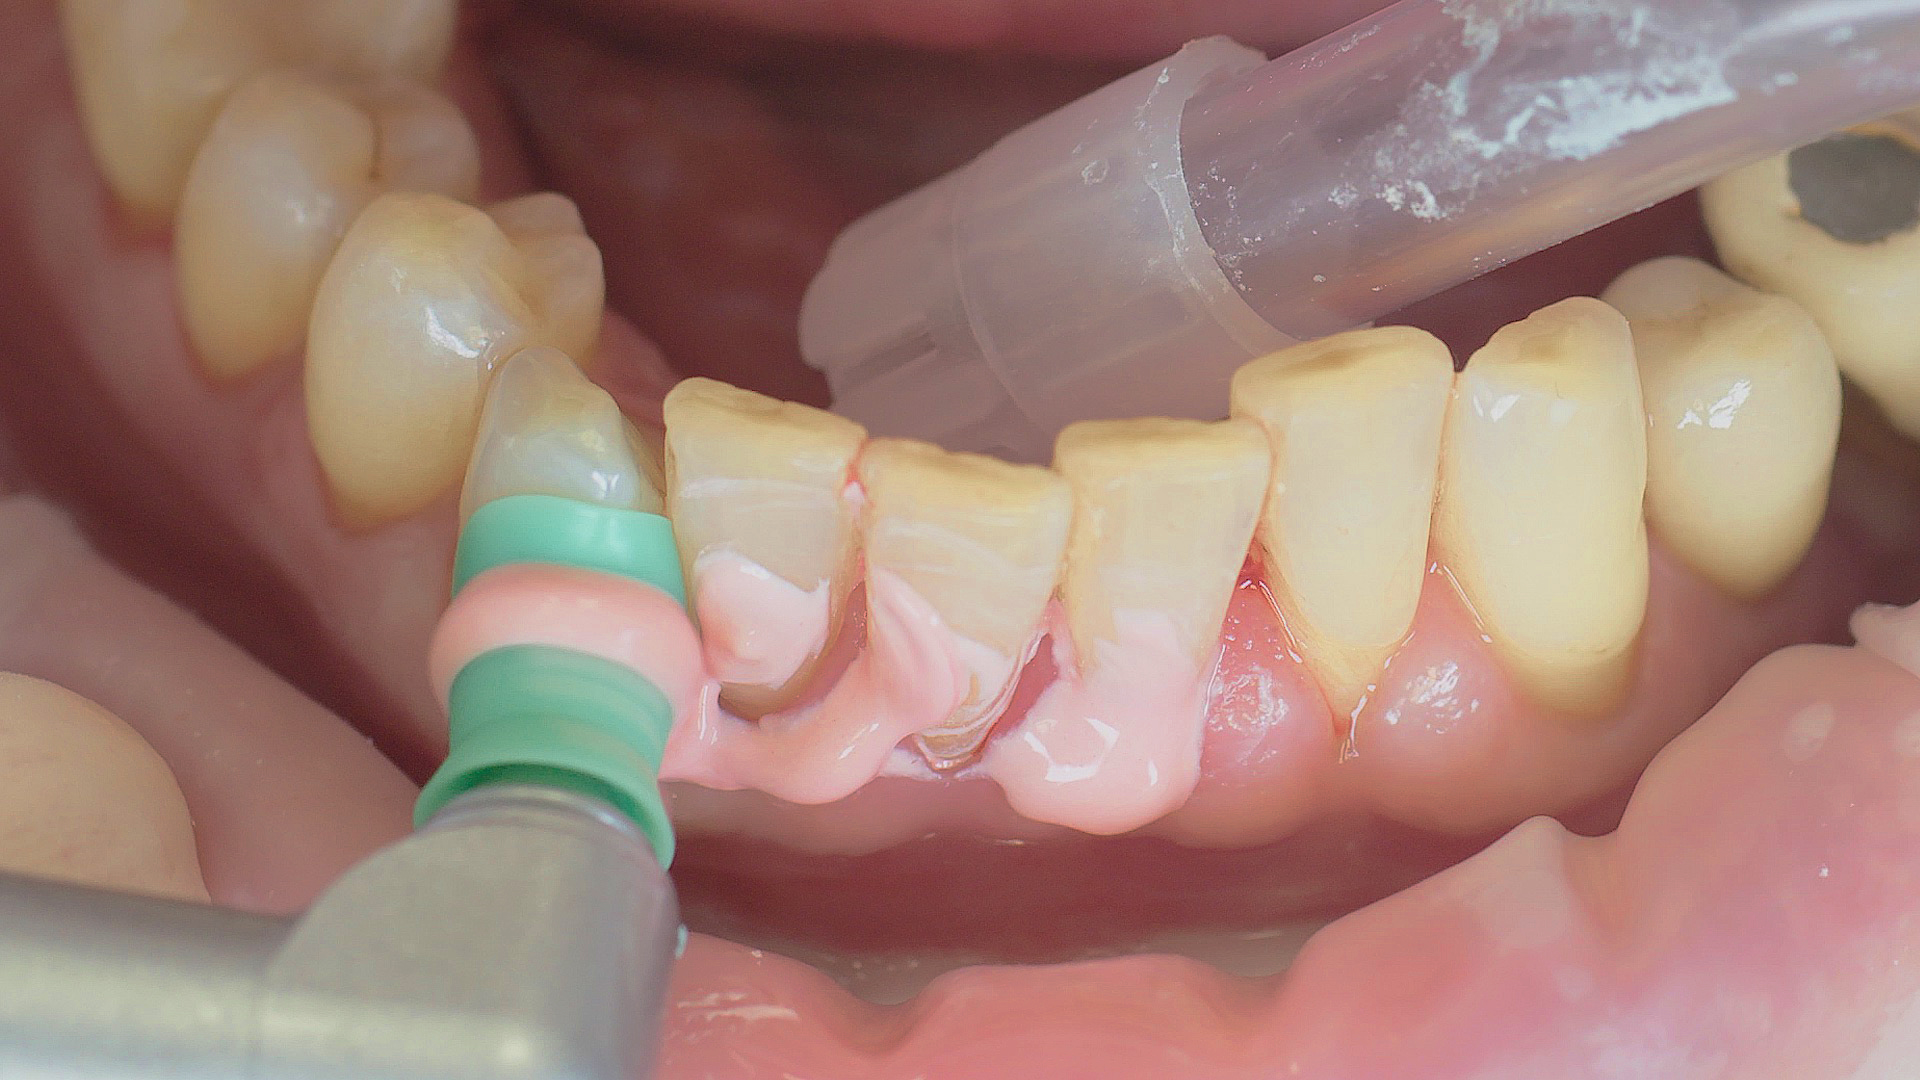

Where necessary, initial periodontal treatment is carried out. First, professional tooth cleaning establishes healthy gingival conditions. In this procedure, calculus (Fig. 1) and biofilm (Fig. 2) are removed as far as the gingival sulcus. In combination with careful instruction on oral hygiene, this gives the patient the basis for long-term freedom from inflammation.15

Rotary cleaning with prophylaxis polishing cups and brushes

Fig. 2: Rotary cleaning with prophylaxis polishing cups and brushes (W&H Proxeo prophylaxis contra-angle handpiece) ensures smooth surfaces on teeth. It enables patients to check biofilm effectively at home.